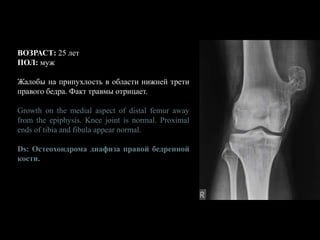

ВОЗРАСТ: 25 лет

ПОЛ: муж

Жалобы на припухлость в области нижней трети

правого бедра. Факт травмы отрицает.

Growth on the medial aspect of distal femur away

from the epiphysis. Knee joint is normal. Proximal

ends of tibia and fibula appear normal.

Ds: Остеохондрома диафиза правой бедренной

кости.